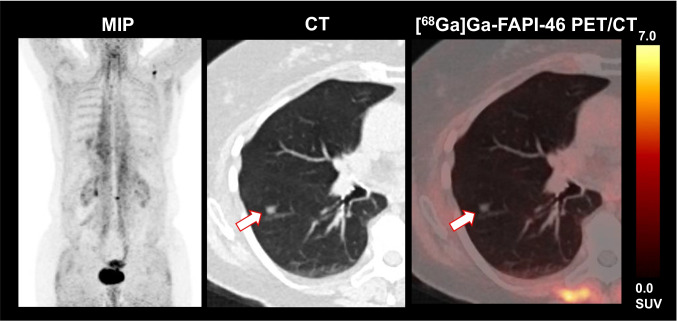

Two out of 15 (13.3%) patients presented with suspected metastatic side on CT imaging, but without relevant FAPI expression: one patient had FAPI-negative lung lesions with a maximum diameter of 0.8 cm; initially, this was rated as highly suggestive of lung metastasis; CT-guided histopathology, however, excluded malignancy (see also Fig. 3). Another patient showed pathologically enlarged loco-regional lymph nodes which were also rated as highly suggestive of malignancy on CT imaging, whereas on PET imaging, these were also FAPI-negative; histopathology during cystectomy could also exclude lymph node metastases and confirmed non-infiltrated, but reactively enlarged lymph nodes.

Fig. 3.

This exemplary patient presented with [68Ga]Ga-FAPI-46-negative lung lesions which have been misinterpreted as metastases in CT. However, histopathology excluded metastases and confirmed reactive, inflammatory lung lesions